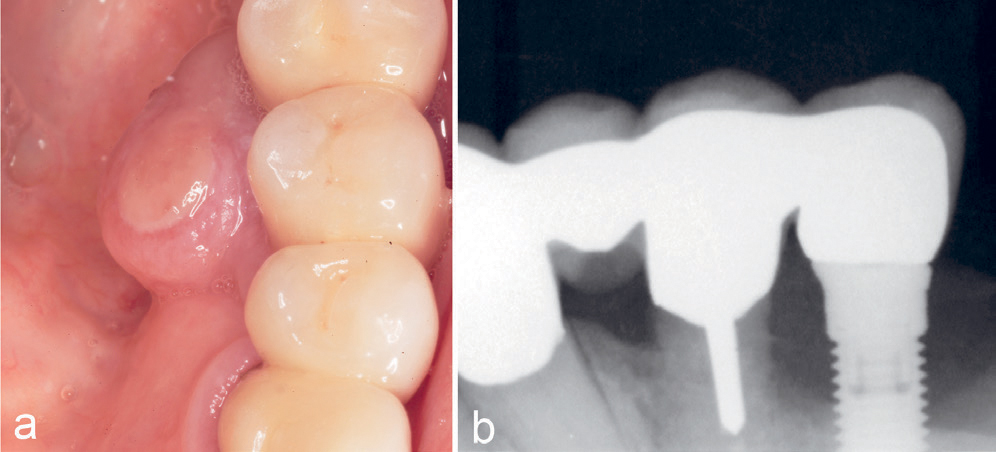

Kasus 15

En 75-årig kvinne var henvist fra tannpleier for vurdering av rød hevelse ved implantat regio 34. Implantatet var innsatt 10–11 år tidligere sammen med et implantat regio 44 som støtte for en protese i en ellers tannløs underkjeve. Det ble funnet en rød hevelse på 7–9 mm distalt for implantatet med kontakt til implantatet (figur 12a) med tendens til peri-implantitt (figur 12b), noe som ble synlig ved biopsi. Lesjonen kom ut i flere biter på grunn av fast tilhefting til implantatet. Diagnosen PKCG ble bekreftet histologisk.

Figur 12. Kasus 15. PKCG distalt ved implantat regio 34 (a) med antydning til peri-implantitt (b).